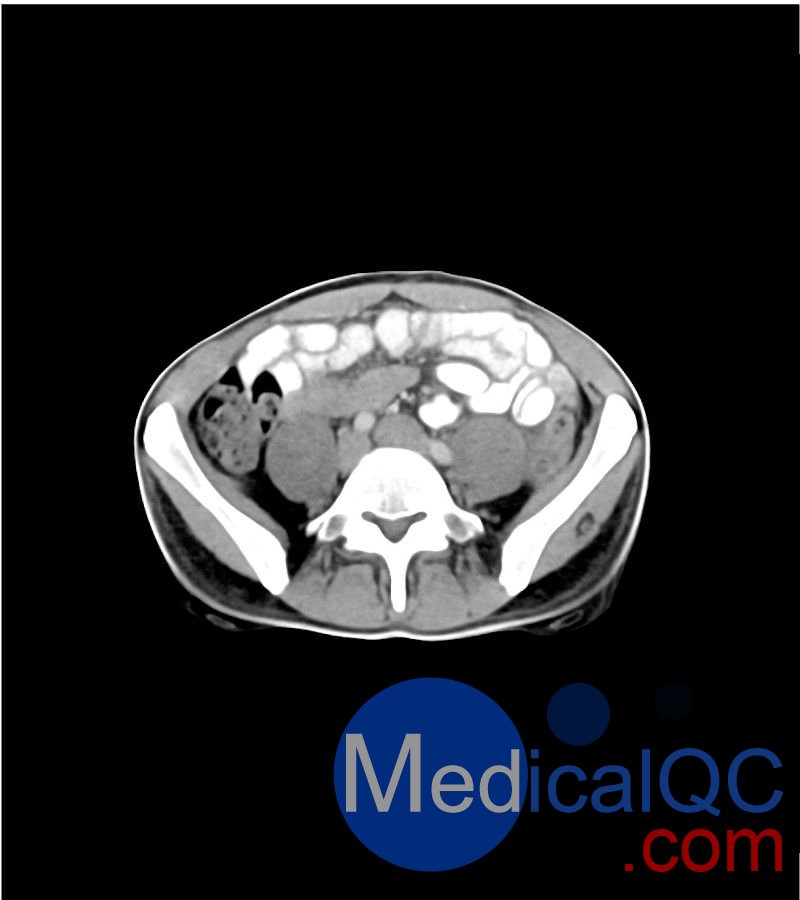

WEK-5501男性腹部模体,WEK-5501男性骨盘模体成像效果图:

WEK-5501男性腹部模体,WEK-5501男性骨盘模体

WEK-5501男性腹部模体,WEK-5501男性骨盘模体可模拟门静脉期的腹部和盆腔增强扫描效果,扫描范围覆盖第一腰椎至会阴区域。

该体模右侧设有髂淋巴结肿块(模拟病灶)。

1. 可对脉管系统、骨骼及软组织进行逼真模拟,涵盖的器官包括肝脏、胆囊、胰腺、脾脏、肾上腺、肾脏、胃、小肠、结肠、膀胱及前列腺。

2. 右侧设有髂外淋巴结肿块(模拟病灶)。